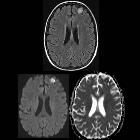

- progressive multifocal leukoencephalopathy

- cerebral toxoplasmosis

- CNS manifestations of AIDS